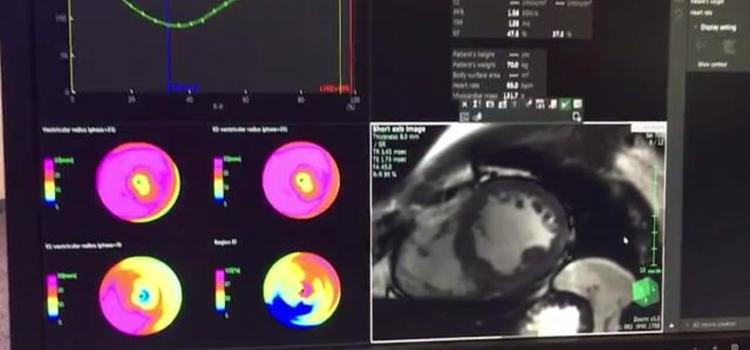

June 12, 2025 — GE HealthCare has announced the combination of GE HealthCare’s proprietary features and algorithms with MIM Encore, marking a significant milestone in its mission to deliver precision care through advanced digital solutions.

June 12, 2025 — GE HealthCare has announced the combination of GE HealthCare’s proprietary features and algorithms with ...